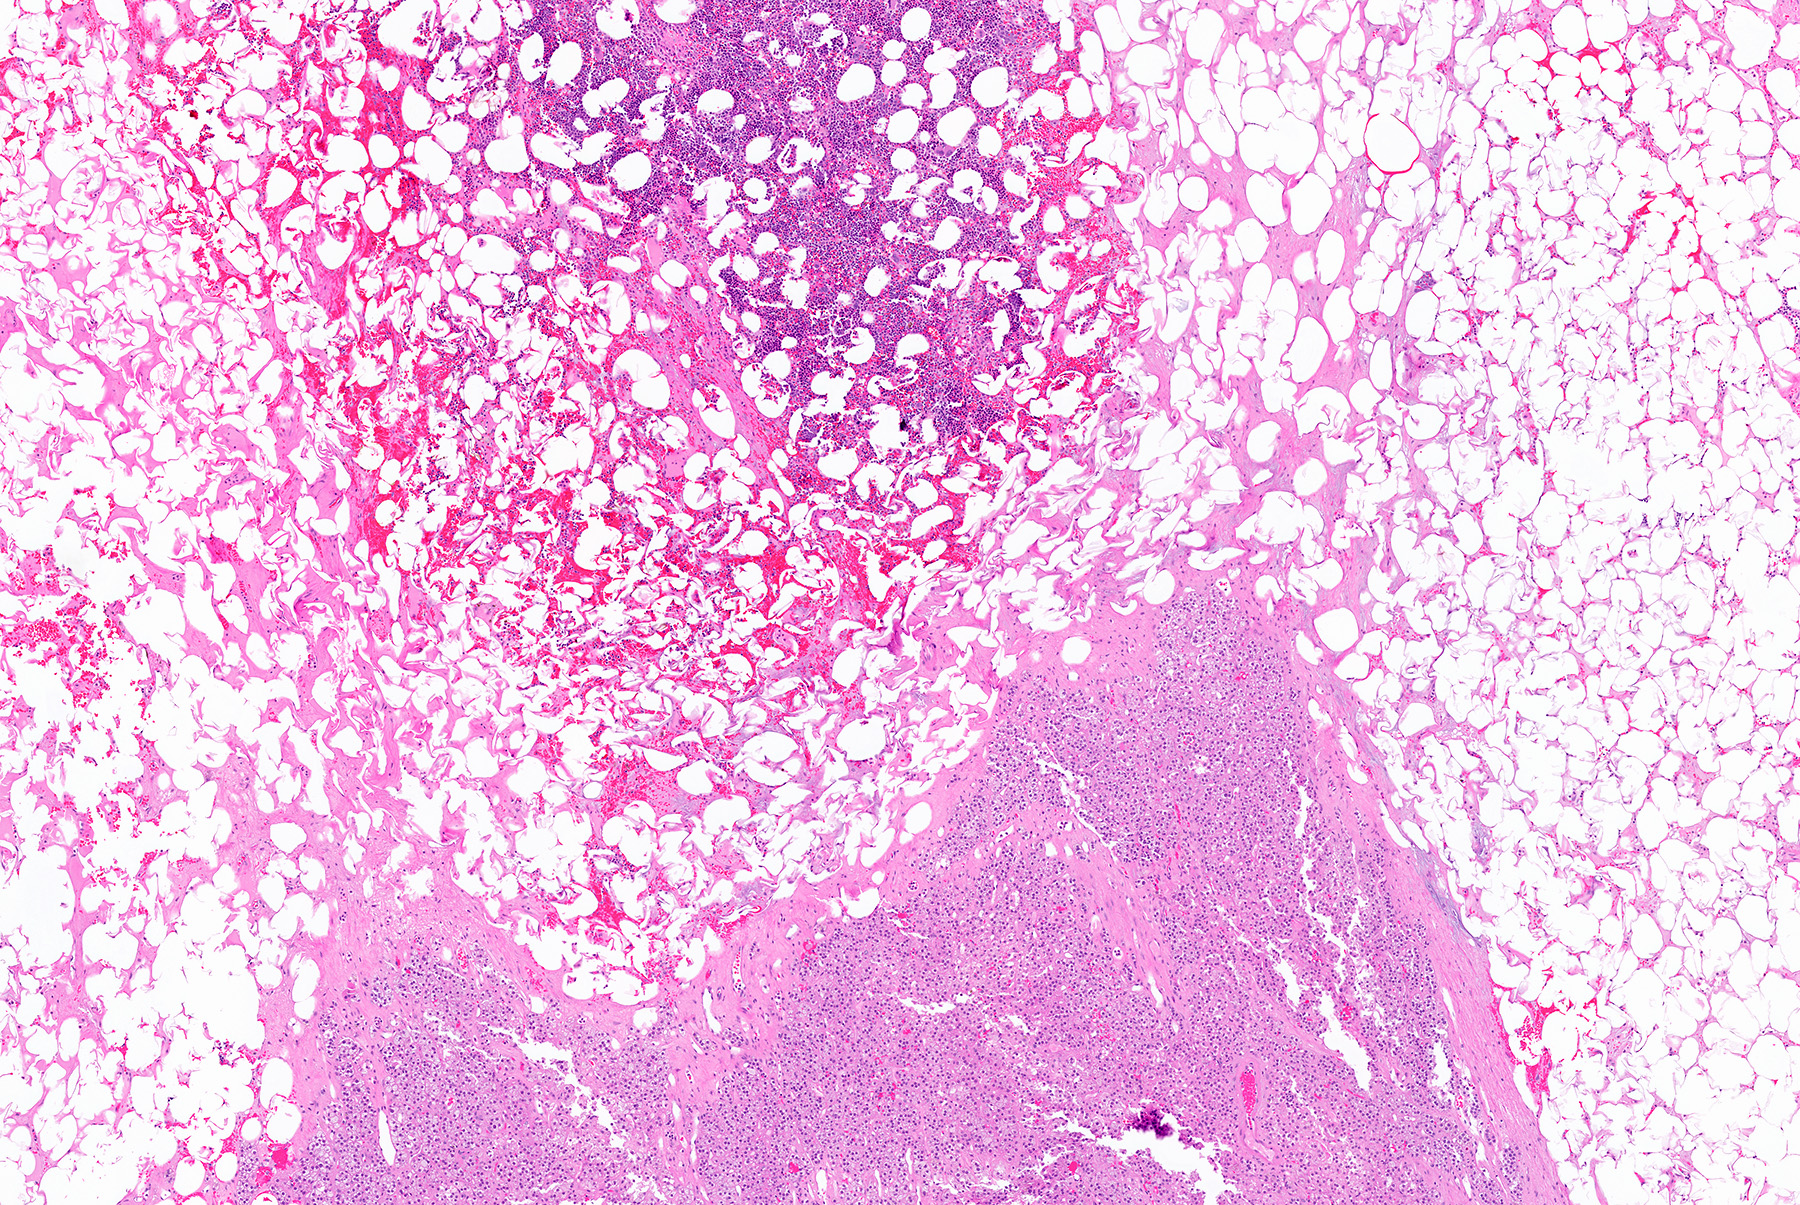

Microscopic (histologic) description

- Mixture of mature adipocytes and extramedullary trilineage hematopoietic cells with full maturation (similar to a hypercellular bone marrow) but often with a markedly increased number of megakaryocytes (Am J Surg Pathol 2006;30:838)

- Calcification, osseous metaplasia and fibrosis can occur

- Rarely may have areas of fibromyxoid degeneration resembling low grade fibromyxoid sarcoma

- Can develop in combination with adrenal cortical tumors, ganglioneuroma, hibernoma, bilateral macronodular adrenocortical disease and congenital adrenal hyperplasia

Microscopic (histologic) images

Contributed by Debra L. Zynger, M.D., Anil Parwani, M.D., Ph.D., O. Hans Iwenofu, M.D., Ph.D. and @ThatGlassTho on Twitter